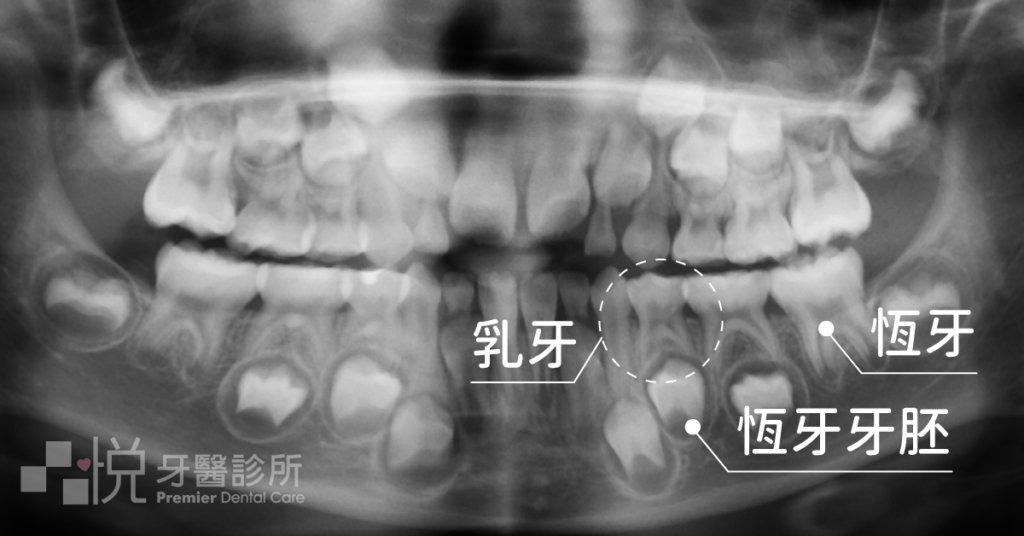

普遍來說,大家都知道換牙後「恆牙」的重要性,但有一部份人卻可能覺得「乳牙」不是很重要吧?不是會換牙嗎?有需要特別關注它嗎?

但其實乳牙在小朋友的生長階段有其存在的必要性,所以本篇文章就來讓大家認識一下,保護乳牙的好幫手 -「乳牙牙套」

乳牙牙套是不會影響換牙的,他就像是一頂保護罩蓋在牙齒的頭和身體上,牙齒的腳在骨頭內並不受影響。

會影響換牙的是牙齒的腳(牙根)的健康程度,所以有時後被細菌感染過而做根管治療的乳牙會有提早或是延後脫落的狀況發生。

所以在換牙階段不需要特別再去拆除牙套,他是會隨著牙根的吸收,跟著乳牙本身一起脫落。